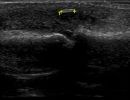

Hand Ultrasound examines joints, tendons, ligaments, nerves, and soft tissues of the hand. Pathologies that can be diagnosed by Hand Ultrasound are numerous, including:

Soft Tissue Pathologies

- Foreign Bodies (glass and wood)